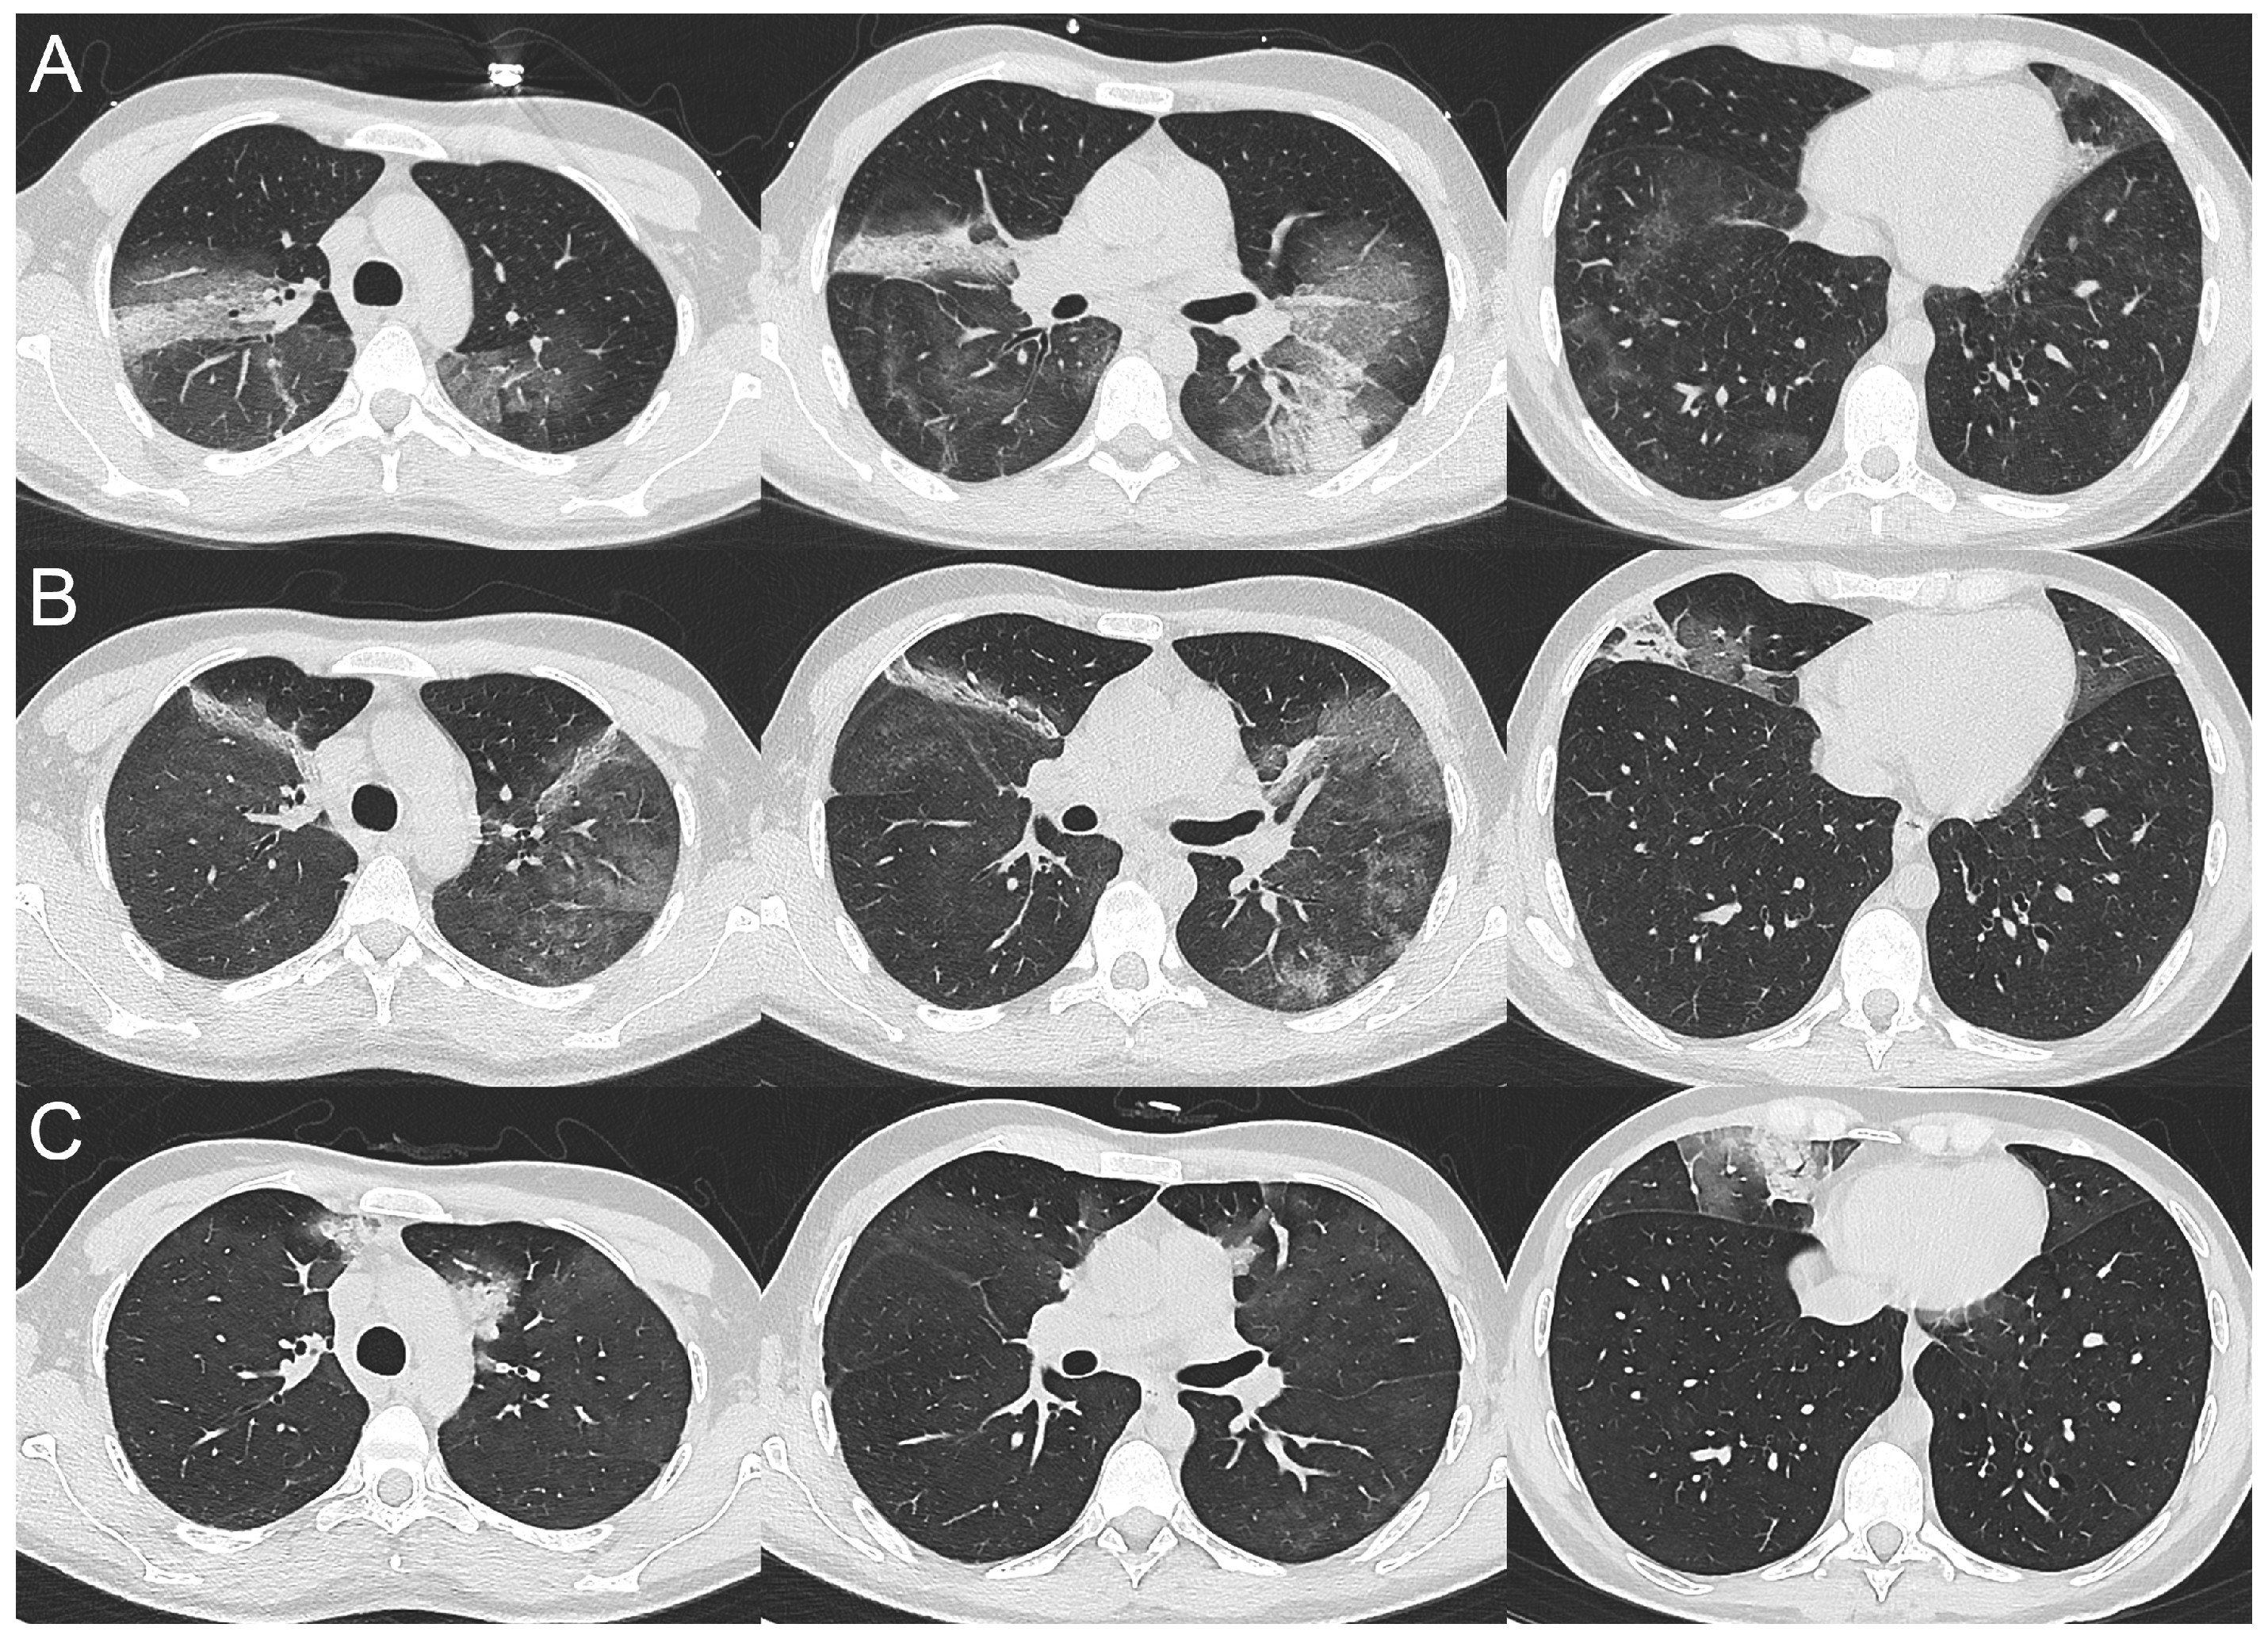

2.1. Case 1